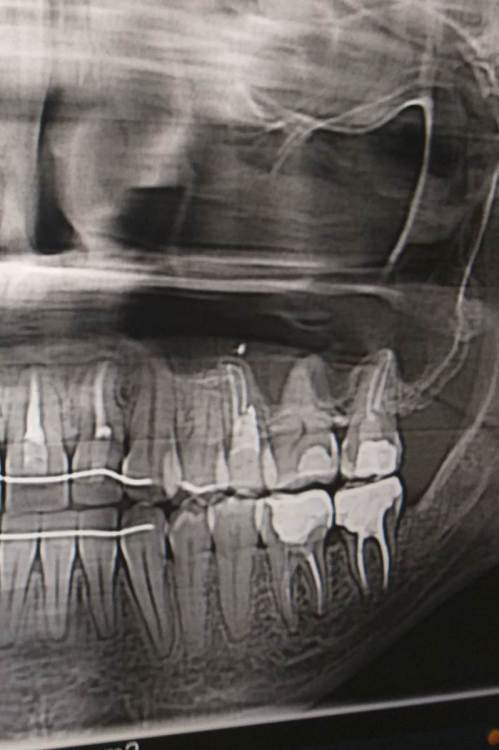

Ирина Артемьева Опубликовано 30 августа, 2022 Поделиться Опубликовано 30 августа, 2022 Здравствуйте! 2 года назад мне лечили 4 и 5 зуб слева наверху: на 4 зубе просто поставили пломбу, на 5 удалили нерв. Впоследствии оказалось что в 5 зубе мне сделали перфорацию. Далее этот зуб мне перелечил другой врач, боли притихли, но иногда зуб поднывал. На данный момент то есть 2 года спустя зуб начал беспокоить сильнее. Днем болит терпимо, а ночью мешает спать, приходится пить обезболивающие. С этими жалобами я пошла к стоматологу, который мне сказал что болеть может не 5, а 4 зуб и посоветовал удалить нерв в 4 зубе. Но я сомневаюсь, т.к. по моим ощущениям болит именно 5 зуб плюс боль отдает в ухо, в голову, также болит лицо около верхней челюсти. Что делать с 5 зубом- удалять или нет? И есть ли смысл удалять нерв в 4 зубе? Жду ваших ответов, т.к. очень устала от этой боли. Снимок какой есть прилагаю Ссылка на комментарий

Doc Опубликовано 31 августа, 2022 Поделиться Опубликовано 31 августа, 2022 Заодно пора подумать о ситуации с 46 зубом (шестерка справа внизу). 1 Ссылка на комментарий